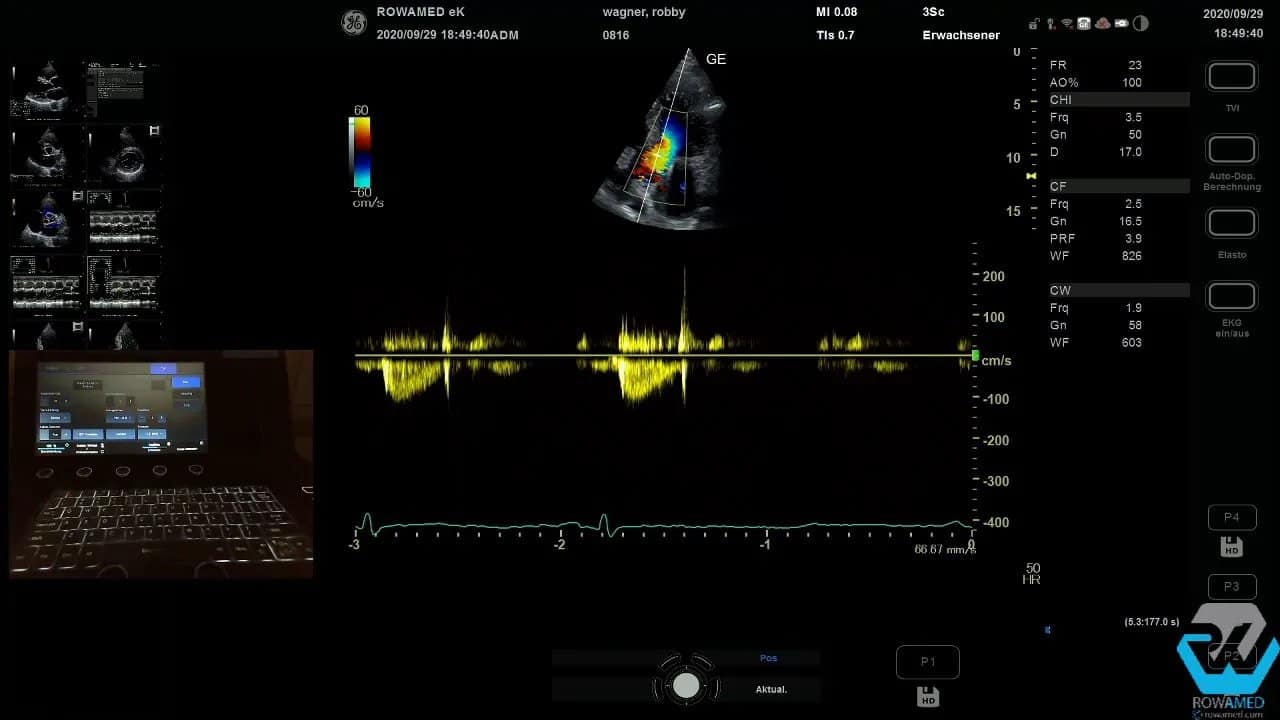

Step 12: Den systolischen pulmonalarteriellen Druck abschätzen

Die Trikuspidalinsuffizienz ist in der Transthorakale Echokardiographie nicht nur ein Klappenbefund, sondern oft der Schlüssel zur Druckabschätzung im kleinen Kreislauf. Mit dem CW-Doppler messen Sie die maximale Regurgitationsgeschwindigkeit über der Trikuspidalklappe, also die TR Vmax.

Im Beispiel betrug sie 2,1 m/s. Das entspricht einem Gradienten von rund 20 mmHg. Addiert man dazu den zentralvenösen Druck, in diesem Fall geschätzt mit 5 mmHg, ergibt sich ein systolischer pulmonalarterieller Druck von etwa 25 mmHg. Das liegt im Normbereich.

Merke:

- TR Vmax messen

- Gradient aus der Dopplergeschwindigkeit ableiten

- ZVD addieren

- Gesamtwert klinisch einordnen

Damit zeigt die Transthorakale Echokardiographie sehr elegant, wie sich aus einem Regurgitationssignal hämodynamisch relevante Zusatzinformationen gewinnen lassen.